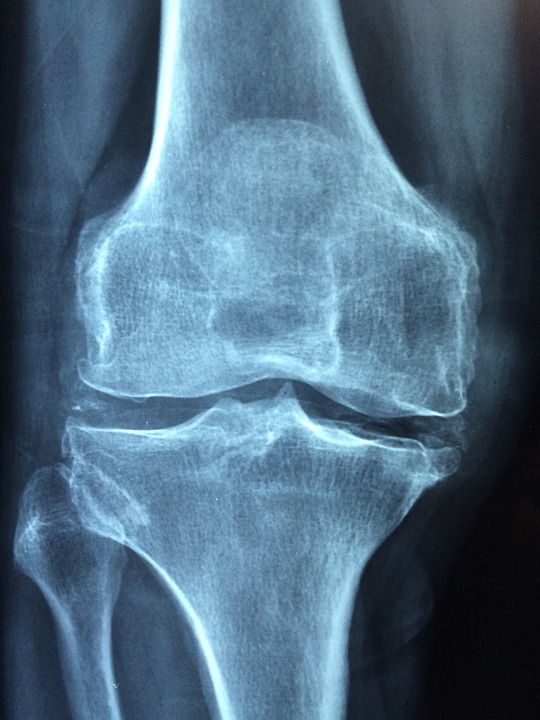

La condropatia è un termine generico, che fa riferimento a una sofferenza, non meglio definita della cartilagine  articolare, ossia quella quantità di materiale cartilagineo che si interpone tra le due superfici ossee di un articolazione rivestendone le superfici. Normalmente ha caratteristiche viscoelastiche, proprietà idonee a proteggere dalle sollecitazioni di attrito tra le superfici stesse e carico sull’articolazione.

La cartilagine degenera fisiologicamente con il tempo, e quando si parla di condropatia si distinguono 4 stadi:

• primo grado: perde elasticità, cambia le sue proprietà;

• secondo grado:  si cominciano ad evidenziare piccole lesioni che non ne modificano l’aspetto complessivo visionabile alla Risonanza Magnetica;

• terzo grado: le  lesioni più profonde si definiscono nettamente all’immagine dell’indagine diagnostica;

• quarto grado: il danno alla cartilagine è importante; il volume appare sostanzialmente ridotto.